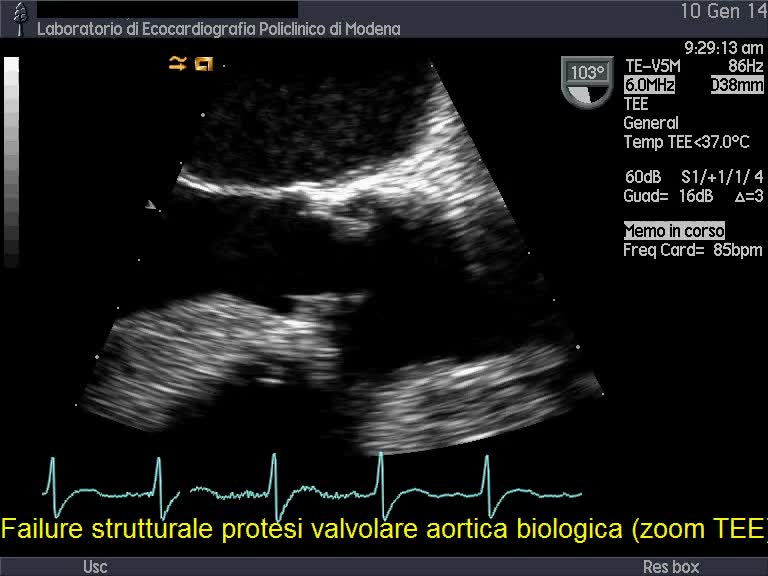

Malfunzionamento di protesiAutore: Camilla Facchini